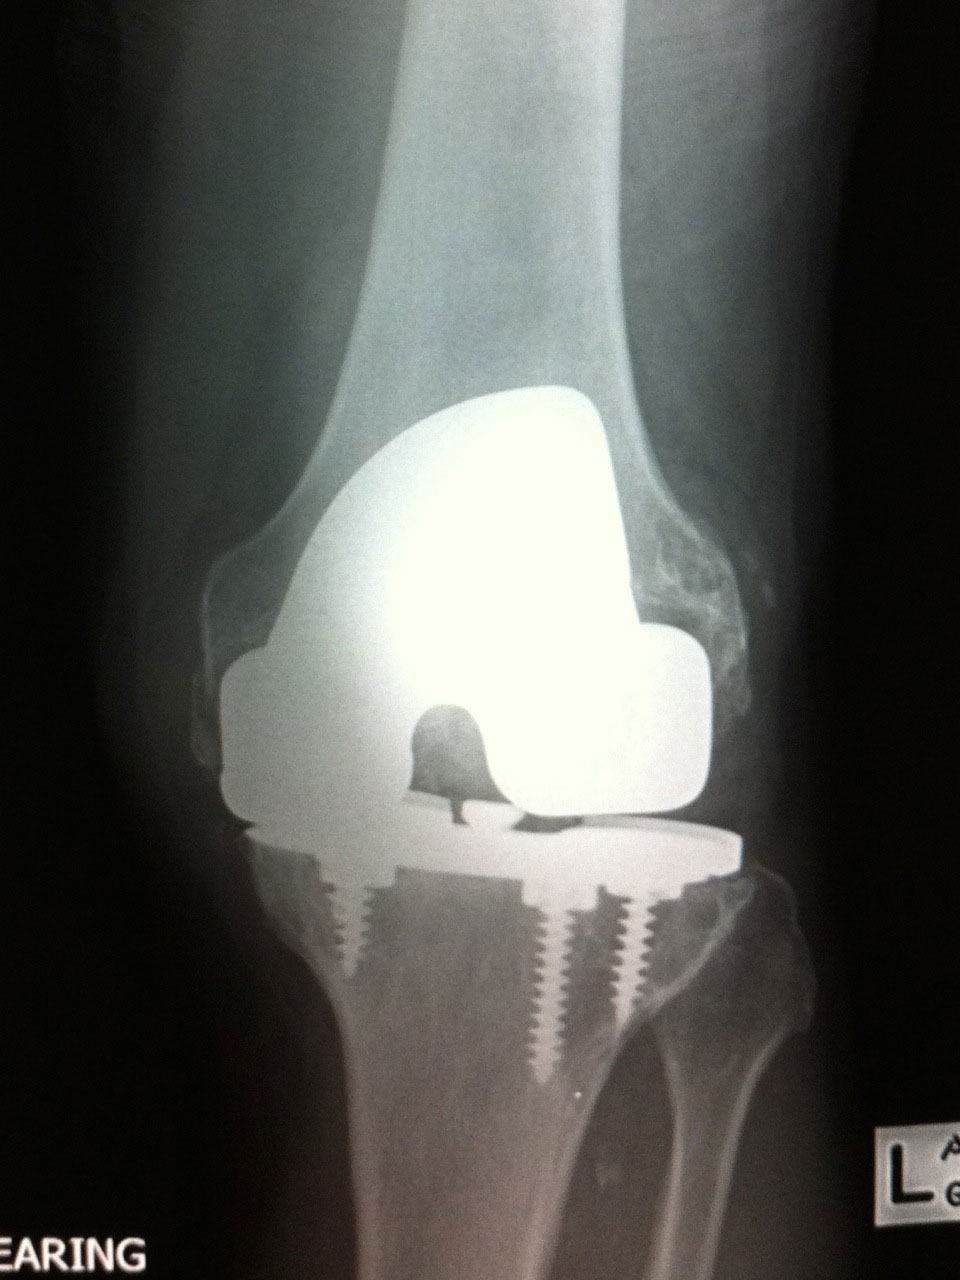

Revision knee replacement is a complex procedure. The failed implants will need removal and this is followed by reconstruction of the joint. This sometimes requires the use of cadaveric bone graft (allograft) and specialized joint implants such as stems, augments, sleeves and hinged implants. Dr Stoita has extensive experience in the use of advanced techniques in these complex and challenging cases to enable the best possible outcome to his patients in Sydney.